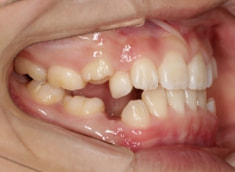

治療後(1年5ヶ月後)

治療開始から11ヶ月